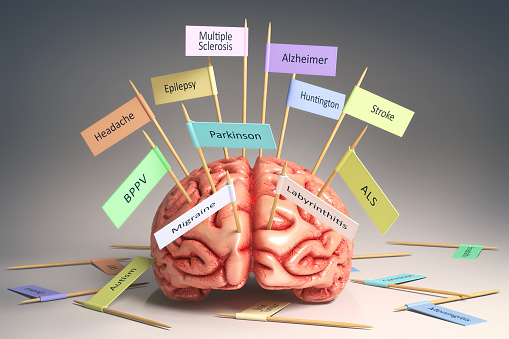

Lewy body dementia, an umbrella term for both Parkinson’s disease dementia and dementia with Lewy bodies

Lew body dementia (LBD) is an umbrella term referring to both Parkinson’s disease dementia and dementia with Lewy bodies. In dementia with Lewy bodies, cognitive symptoms interfering with daily living present themselves before or within one year of Parkinson’s-like movement problems. In Parkinson’s disease dementia, cognitive symptoms usually don’t appear until after a year of ...click here to read more